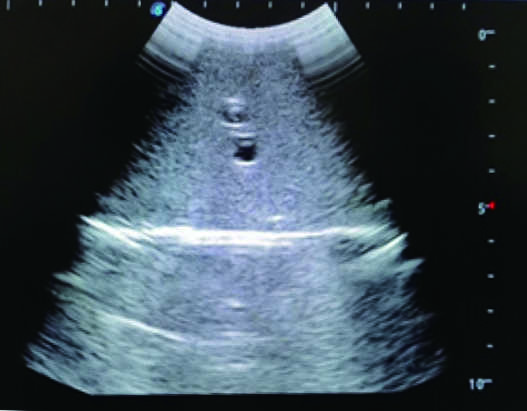

2) Real clinical ultrasound images with clear anatomical structures like intestines, part of the liver, arteries and veins, etc.